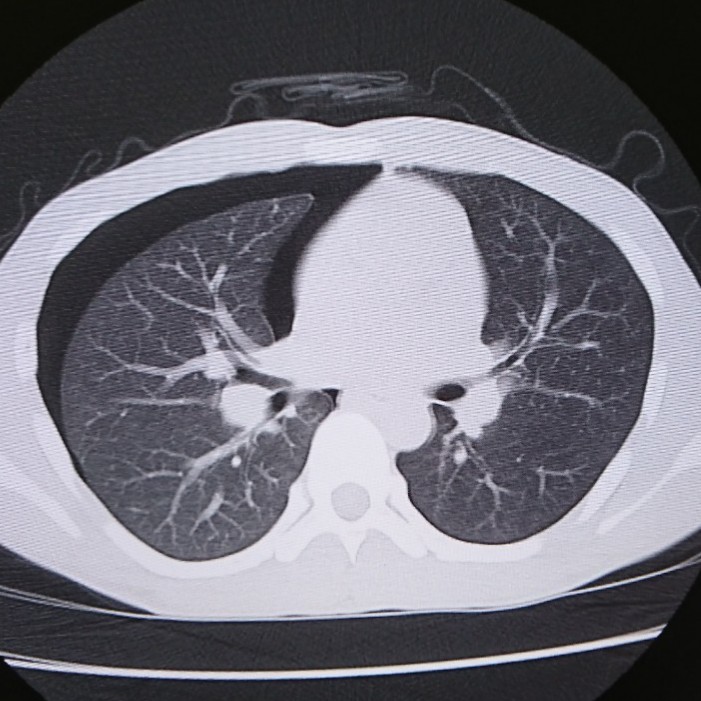

CTを撮れば一目瞭然です。

真っ黒のところは穴が空いてできた隙間です。

なんか苦しそう